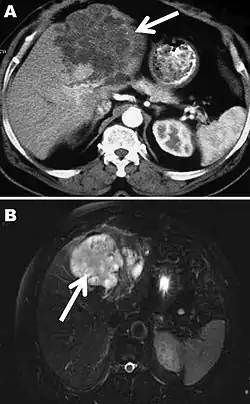

The diagnosis of polycystic echinococcosis involves isolating the protoscoleces during surgery or after the patient's death in order to identify E. vogeli. Imaging, such as ultrasound and CT scans, can also be used to identify polystytic structures, but this method is not preferred as images are similar to other types of echinococcosis and liver cancer. New studies show that PCR may identify E. vogeli in the patient's tissues.[5]

Polycystic echinococcosis (PE) is an extremely lethal helminthic disease in humans, which is caused by the larval form of E. vogeli. Type I PE consists of polycystic masses in the liver and abdominal cavity. Type II also has polcystic masses in the liver and abdominal cavity, but includes hepatic insufficiency. Type III has polcystic masses in the liver and chest cavity. In type IV polycystic masses occur only in the mesenteries. Type V has calcified cysts in the liver and lung.[4] Type II seems to have the highest mortality rate due to the complications involved with hepatic insufficiency. Due to the similarities between liver cancer and polycystic echinococcosis, PE is hard to diagnose and could be deadly when metastasized to other organs.